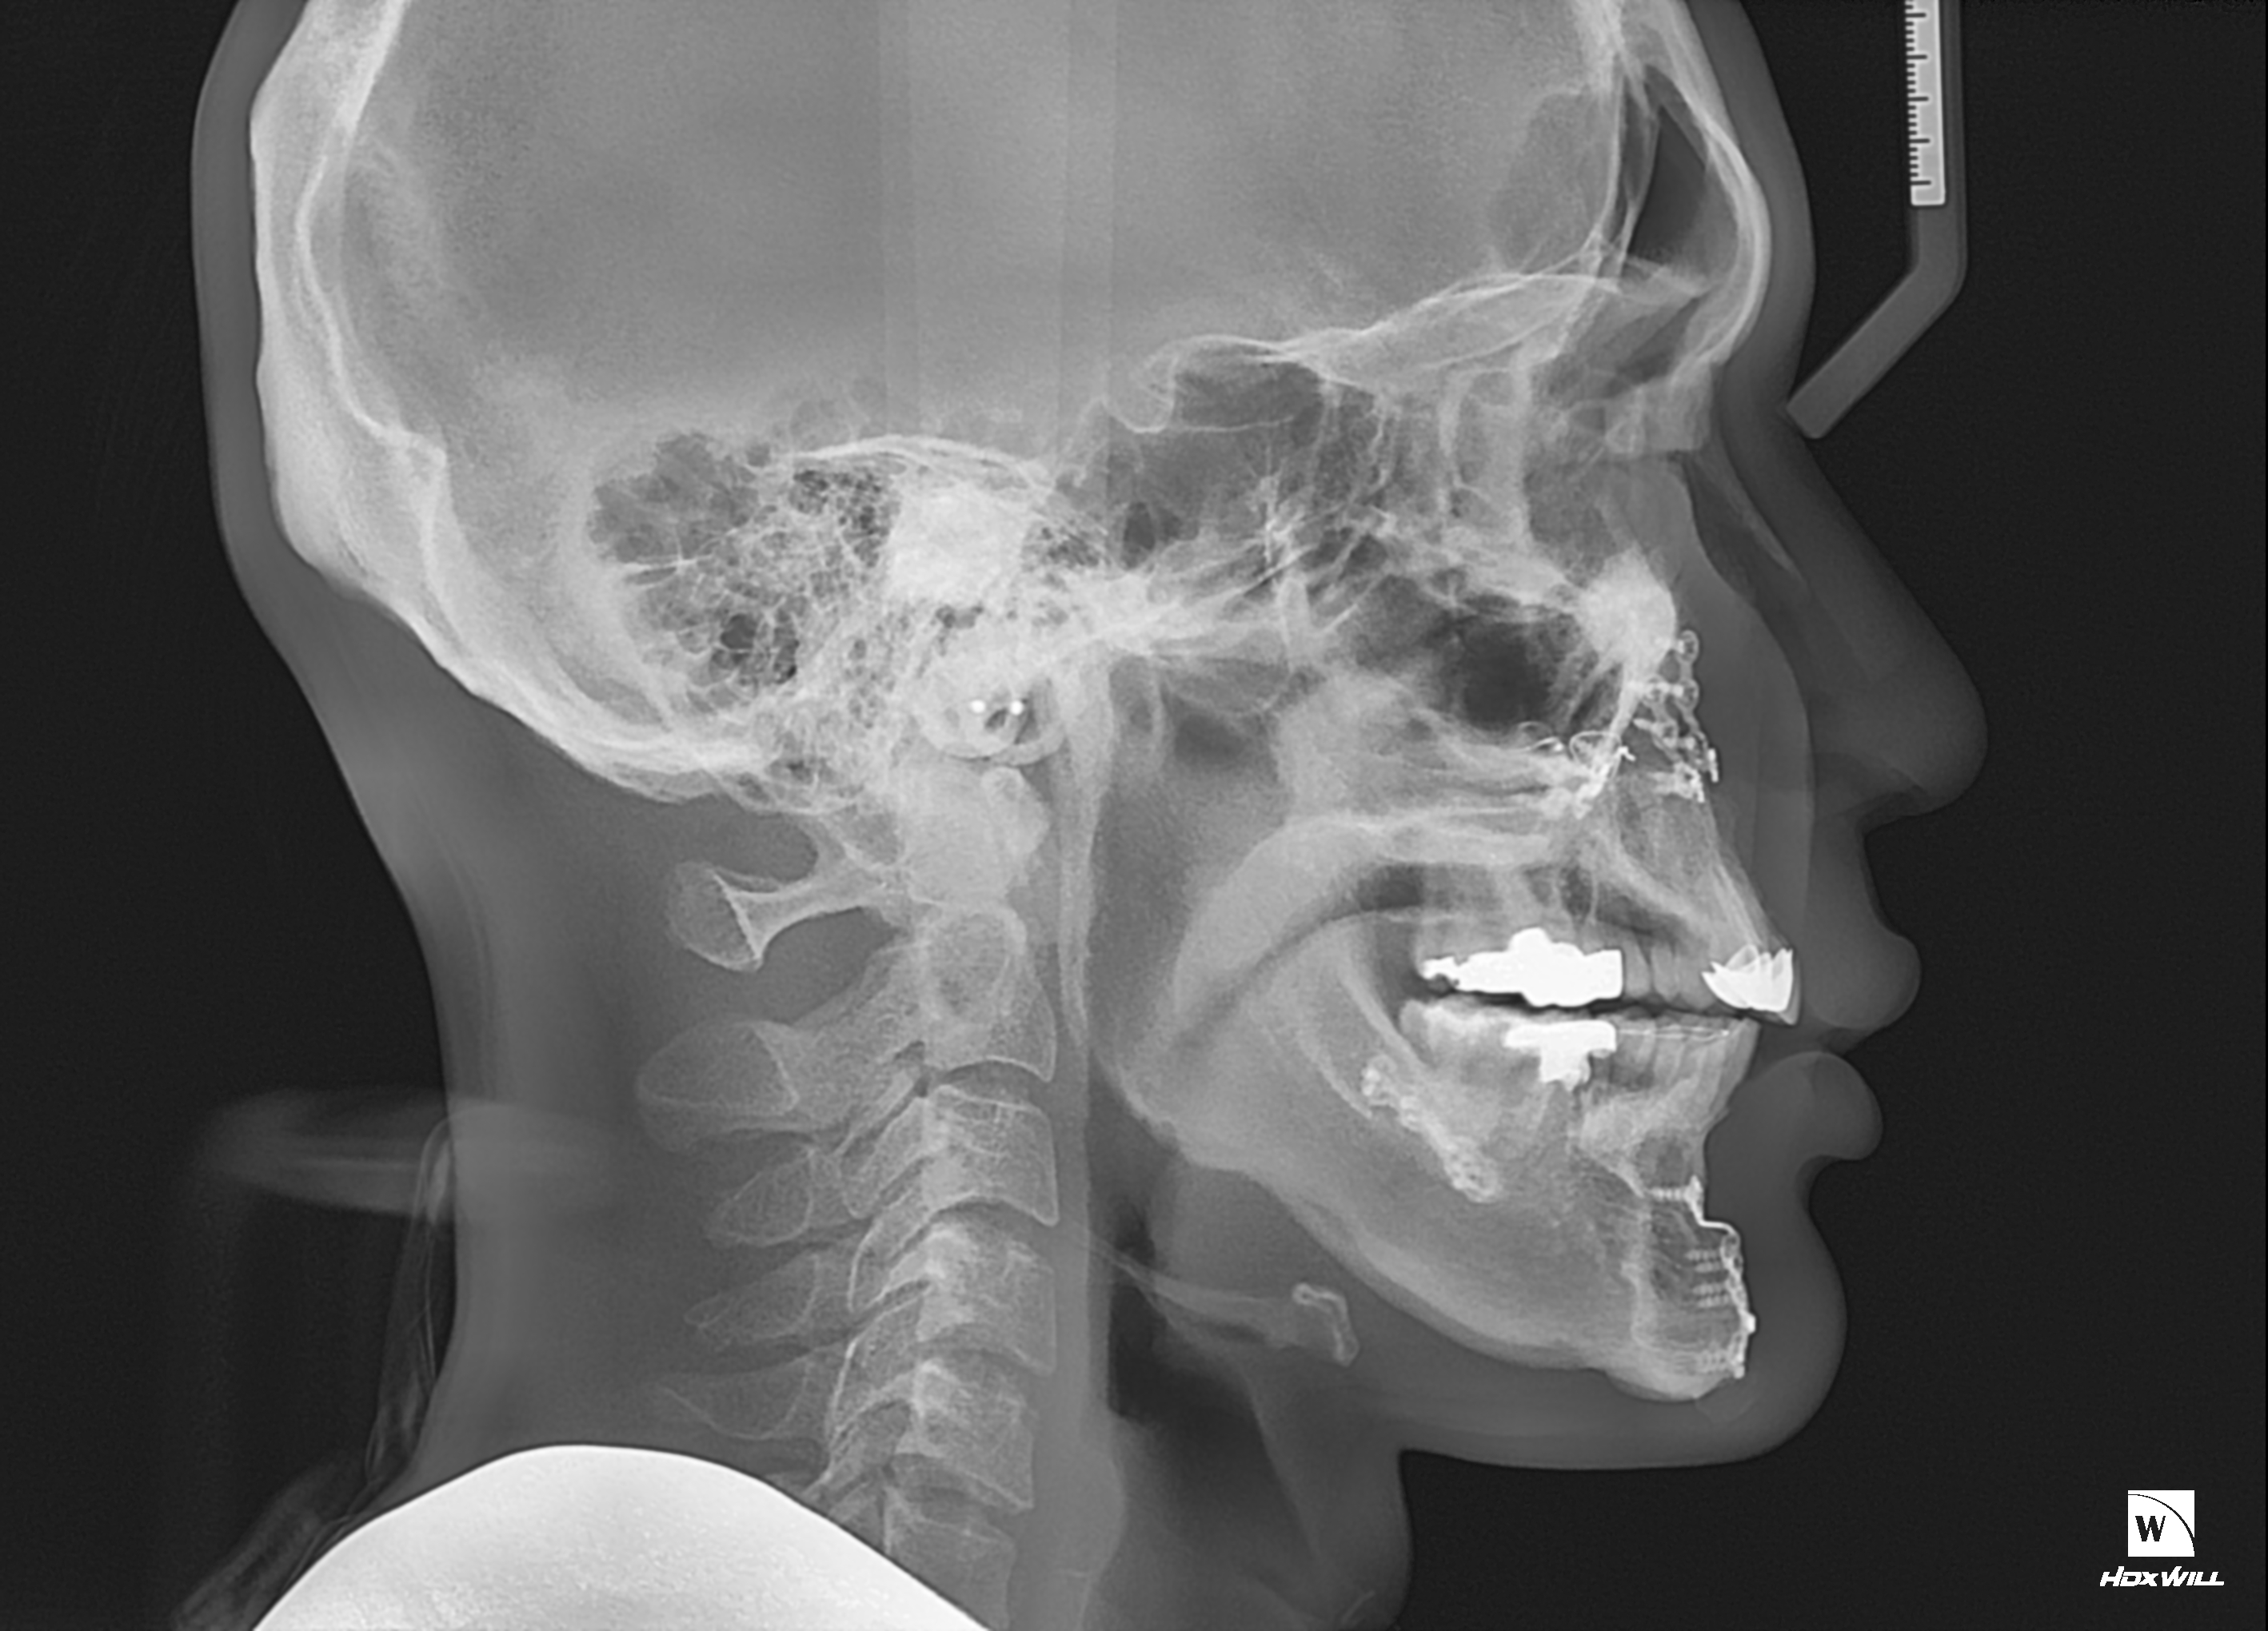

1. 현재 제가 수술 전후 ct를 올리겠습니다

2. 일차 양악 수술후 경미한 주걱턱 때문에 쉐이빙을 했는데 효과는 미미했습니다 진짜 쉐이빙은 효과가 미흡

3. 그 후 어드벤스를 3mm정도 했습니다

4. 현재 주걱턱 처럼 보여서 돌아버리겠습니다..

5. 음 어느 선생님 말을 빌리면 턱끝 절골라인이 너무 아래서 절골되어서 그런거다 신경선으로 부터 5~10mm정도 아래서 절골후 약간 사선으로 2mm 정도만 전진시키면 두꺼운 근육이 얇아지면서 좀 편해진다 이게 맞는말인가요???

6. 아니면 지금 상태에서 다시 절골한곳 다시 절골해서 뒤로 후퇴시켜야되나요?

7. 지금 현재 턱끝 포지션은 좋은가요?

8. 아래 제가 도완 한 대로 수술하면 어떨까요? 길이도 줄이면서 후퇴도 시키고